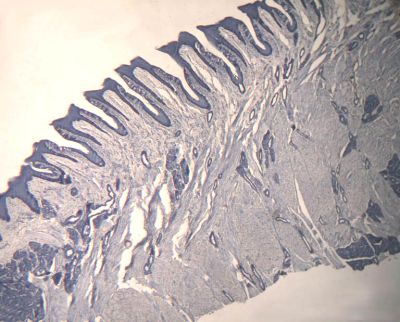

Tongue - histology slide

This histology slide shows foliate papillae with taste buds.

Histology slide courtesy of Florida State University.